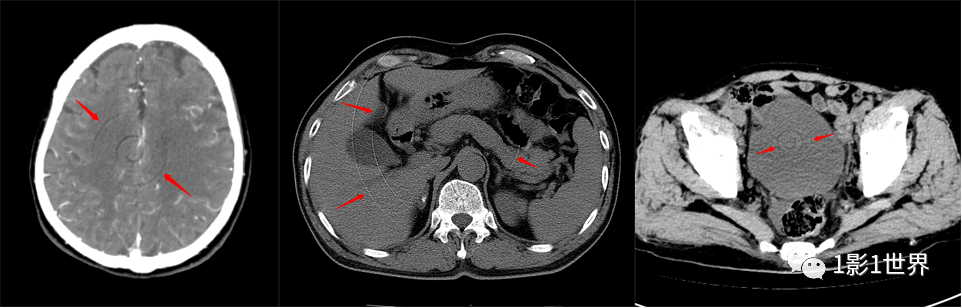

,避免密度对比过大的物体相接触。部分容积效应,是影像断层扫描中的一个概念,因为层厚的影响,相邻组织间出现重叠,表现出异常影像。

左肾前方结节,5mm层厚图像上似为肠管延伸过来,2mm薄层图像显示为副脾。